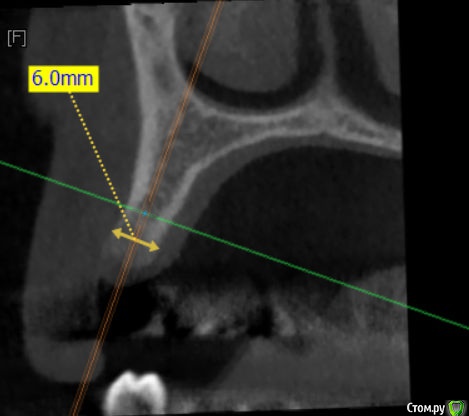

Kazankov.Egor Опубликовано 17 мая, 2018 Поделиться Опубликовано 17 мая, 2018 Господа ветераны, делать нкр или поставить винт 3.3+сст? Бояться ли в данном случае угла (в связи с функцией коронки)? Ссылка на комментарий

Nazim_NV86 Опубликовано 17 мая, 2018 Поделиться Опубликовано 17 мая, 2018 Главное вестибулярно кортикалку не испортить. 3.3-3.5 легко закрутится. Чуть расщепить можно, +1мм будет. Ссылка на комментарий

Evikrol Опубликовано 17 мая, 2018 Поделиться Опубликовано 17 мая, 2018 3,5 на 11,5 или 13 мм и заглубится + сст 3 Ссылка на комментарий

Kazankov.Egor Опубликовано 17 мая, 2018 Автор Поделиться Опубликовано 17 мая, 2018 Главное вестибулярно кортикалку не испортить. 3.3-3.5 легко закрутится. Чуть расщепить можно, +1мм будет.Распилы не делать вертикальные? Просто сделать горизонтальный по вершине гребня и расширить? Как в случае расщепа модифицируется протокол сверления? Планирую BL 3,3#13.Лучший ли выбор для такой ситуации? Ссылка на комментарий